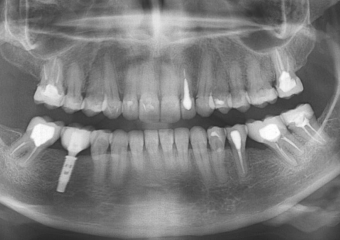

Raio X inicial apresentando ausência do molar inferior direito

Raio X do implante

Raio X com prótese fixa em porcelana sobre implante Cone Morse